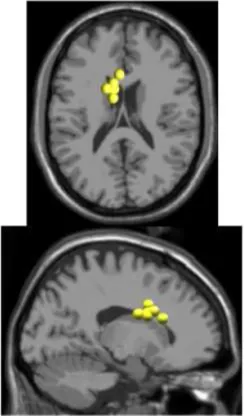

As expected the average treadmill belt velocity was more variable during active treadmill walking, regardless of command speed (Figure 3A). Average pelvis velocity in the sagittal plane was similar for the slow and fast walking commands, indicating the participants were able to match the desired treadmill command speed accurately during the steady walking tasks (Figure 3B). The k-means clustering resulted in seven spatially distinct clusters of electrocortical dipole sources, plus one additional outlier cluster (Table 1). We identified the Brodmann areas represented within each cluster from the Talairach atlas (Lancaster et al., 2000); dipoles were located within ±3 mm cube range of 14 Brodmann areas across the seven clusters. We performed spectral and time-frequency analysis on 6/7 clusters with the RPM cluster omitted because it did not contain ICs from a majority of the participants.

| Posterior parietal | Left motor | Right motor | Left premotor | Right premotora | Anterior cingulate | Prefrontal | |

![]() | ![]() | ![]() | ![]() | ![]() | ![]() | ![]() | |

| Number of subjects | 7 | 5 | 5 | 5 | 3 | 5 | 5 |

| Number of ICs | 9 | 5 | 5 | 5 | 4 | 5 | 5 |

| Brodmann areasb | 5, 7, 31 | 3, 4, 31 | 1, 3, 4, 6 | 6, 8, 24 | 6, 24 | 24, 32, 33 | 9, 10, 32, 46 |

Clusters of dipolar sources fit to independent components.

aThe RPM cluster was omitted from analysis because it did not contain ICs from a majority of the subjects.

bBrodmann Areas reflect those found within a ±3 mm search range of all individual dipoles within a cluster.